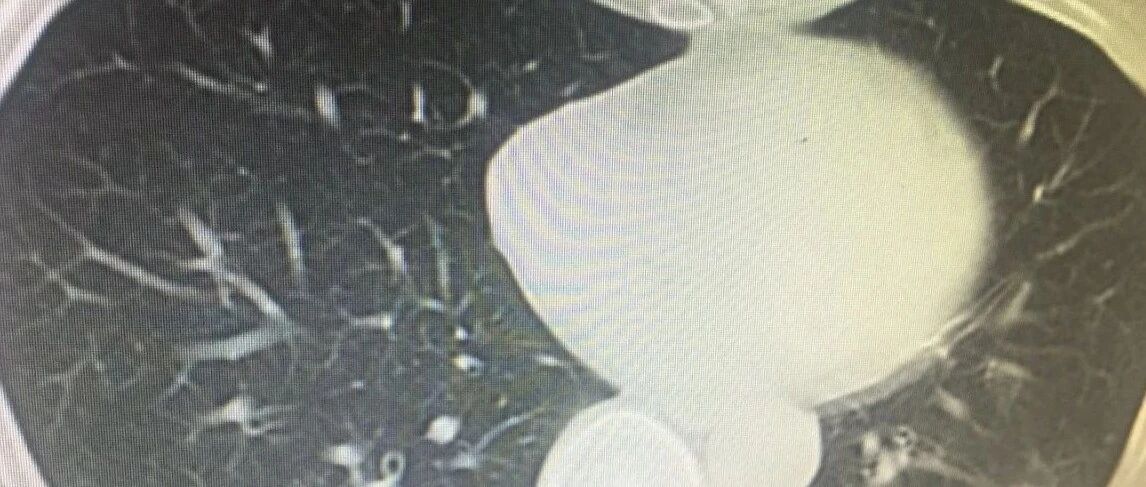

根据一份涉及北京、重庆及广州3个地区城镇的、不太大的调查报告显示:这三个地区被抽中的成年男性中,ED总患病率为26.1%,40岁之后患病率达到40.2%。

图片来源:文献截图